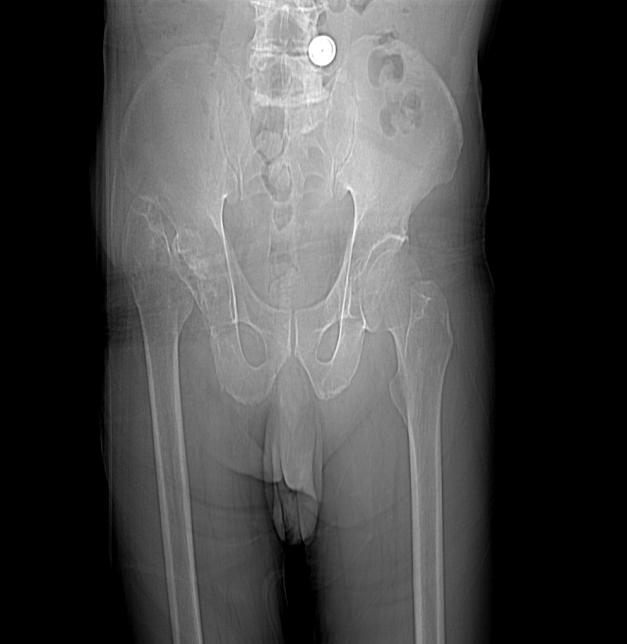

患者入科后,对患者进行详细的检查,患者跌倒在地不能起来需要考虑是否是脑卒中,所以就对患者进行了神经系统查体,患者神志清楚,表情呆滞,不能对答,但是患者口角无歪斜,双上肢及左下肢可见活动,右下肢未见明显活动,病理征也是阴性,所以考虑脑卒中的依据不充分。这种情况需要考虑患者是否因为局部病变引起,比如右髋关节是否有骨折,因为老年人很容易在发生跌倒的情况下出现骨折,加之该患者有严重的痴呆,对疼痛不敏感,所以对患者右下肢进行了查看,髋部无皮下淤血,按压可见患者用手阻挡并有痛苦的表情,在看看右下肢有缩短外旋的情况,所以就高度怀疑存在骨折,安排患者进行了骨盆CT检查,提示右侧股骨颈骨折,所以疾病诊断明确了。

紧接着请了骨科会诊,外科建议患者行股骨头置换手术,患者家属考虑到患者年龄大,身体功能差,不愿意手术治疗,表示愿意保守治疗,在外科的指导下给予患者右下肢皮肤牵引,保持患者右下肢的功能位,同时给予止痛对症,加用钙剂抗骨质疏松,防止静脉血栓的形成,进行了肢体的康复训练。经过2周的住院治疗,患者右下肢复查CT骨折稳定,但因为患者右下肢骨折未下床活动。

患者子女因为考虑患者年龄及身体状况拒绝了手术治疗,采取了内科保守治疗,皮肤牵引治疗可以防止疼痛加剧和肢体挛缩,对减轻局部水肿都很有帮助。患者经过止痛和抗骨质疏松的对症处理,病情稳定,复查骨盆CT未见骨折的加重,移位情况有所改善,未发生褥疮及深静脉血栓情况,机体功能渐渐恢复,但是由于长时间未下床活动,需要继续加强床上的日常护理。